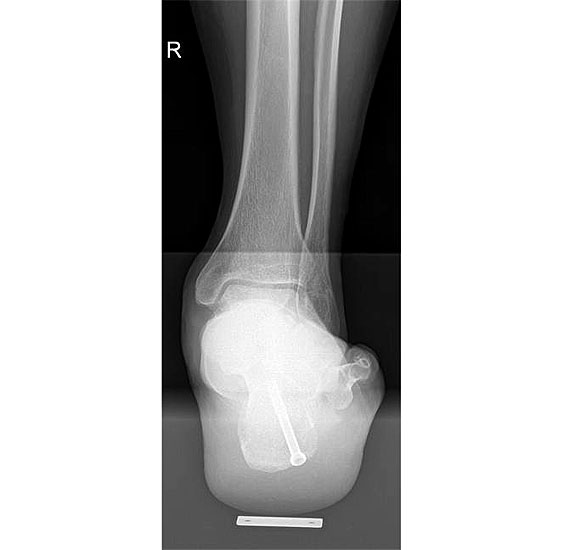

Operationstechnik

715.<br> Für die medialisierende Calcaneusosteotomie wird ein bogenförmiger Hautschnitt in Höhe des hinteren Fersenbeines gesetzt, die Subcutis bis zum Fersenbein durchtrennt und dieser bogenförmige Lappen nach ventral präpariert. Dadurch kommt es zu einem Schutz des Nervus suralis, welcher gemeinsam mit den Peronealsehnen nach vorne gehalten wird.<br> Es wird nun das Fersenbein mit einem Wundspreizer eingestellt und cranial sowie caudal mit 2 Hohmannhaken umfahren.<br> Dann wird das Fersenbein mit der oszillierenden Säge osteotomiert, mit dem Meißel und dem Wundspreizer distrahiert.<br> Danach wird das Fersenbein ca. 1 cm nach medial verschoben, unter Vermeidung der Cranialisierung des hinteren Calcaneus . Dann wird von dorsal über eine Hautstichincision der Bohrdraht für die 4,5mm (- 6,5 mm) kanülierte Schraube eingebracht und über die Osteotomie in den vorderen Calcaneusanteil vorgeschoben.<br> Kontrolle im Bildwandler in 2 Ebenen. Wenn die Bohrdrahtlage gut ist Überbohren für die kanülierten Schrauben und Eindrehen der Schraube. (Alternativ kann an Stelle der Schraubentechnik auch eine Fixation mit Stufenplatten oder Ähnlichem verwendet werden).<br> Wundverschluss am lateralen Zugang und über der Stichincision.</p>"> 715.<br> Für die medialisierende Calcaneusosteotomie wird ein bogenförmiger Hautschnitt in Höhe des hinteren Fersenbeines gesetzt, die Subcutis bis zum Fersenbein durchtrennt und dieser bogenförmige Lappen nach ventral präpariert. Dadurch kommt es zu einem Schutz des Nervus suralis, welcher gemeinsam mit den Peronealsehnen nach vorne gehalten wird.<br> Es wird nun das Fersenbein mit einem Wundspreizer eingestellt und cranial sowie caudal mit 2 Hohmannhaken umfahren.<br> Dann wird das Fersenbein mit der oszillierenden Säge osteotomiert, mit dem Meißel und dem Wundspreizer distrahiert.<br> Danach wird das Fersenbein ca. 1 cm nach medial verschoben, unter Vermeidung der Cranialisierung des hinteren Calcaneus . Dann wird von dorsal über eine Hautstichincision der Bohrdraht für die 4,5mm (- 6,5 mm) kanülierte Schraube eingebracht und über die Osteotomie in den vorderen Calcaneusanteil vorgeschoben.<br> Kontrolle im Bildwandler in 2 Ebenen. Wenn die Bohrdrahtlage gut ist Überbohren für die kanülierten Schrauben und Eindrehen der Schraube. (Alternativ kann an Stelle der Schraubentechnik auch eine Fixation mit Stufenplatten oder Ähnlichem verwendet werden).<br> Wundverschluss am lateralen Zugang und über der Stichincision.</p>" srcset="/assets/images/a/3-raswd6qgkh6s353.jpg 1x, /assets/images/g/3-exngvjjv83x827d.jpg 1.5x, /assets/images/w/3-836r57qt8j3eh0w.jpg 2x" width="270" height="240" loading="lazy">

Abbildung 3

Abbildung 4

Komplikationen: In 1 Fall zeigte sich eine temporäre Läsion des Nervus suralis, welche jedoch nach 3 Monaten komplett ausgeheilt war. Es fanden sich keine Osteolysen, keine Schrauben- oder Dübelprobleme, keine Zystenbildung.

Es konnte, bei präoperativer Unfähigkeit zum einbeinigen Zehenspitzenstand, beim letzten Follow up in 62% der Fälle ein schmerzloser einbeiniger Zehenspitzenstand erreicht werden. Der Saltzmann-Winkel konnte von präoperativ 11° (7-17°) auf 3° (1-8°) korrigiert werden. Der seitliche Metatarsale I Winkel wurde von 18° präoperativ (13-23°) auf 7° (5-13°) postoperativ korrigiert. Der talonaviculare Überdeckungswinkel konnte von präoperativ 10° (4-18°) auf postoperativ 7° (2-15°) reduziert werden.